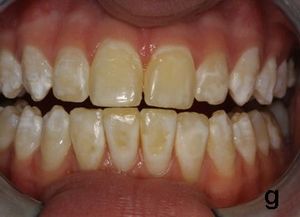

경미한 반상치의 경우, 치아 법랑질 표면은 대체로 손상되지 않고 단단하며 매끄럽지만, 경계가 불분명한 불투명한 흰색 반점이나 주름선(perikymata)을 따라 좁은 흰색 선이 나타나는 특징을 보인다.[7] 상태가 심해질수록 치아 표면 아래의 법랑질은 더욱 다공성(구멍이 많아지는 상태)이 된다. 이로 인해 법랑질은 황색이나 갈색으로 변색되거나, 충치와 유사하게 움푹 들어간 흰색-갈색 병변이 여러 개 나타날 수 있다. 이러한 외형은 흔히 "얼룩덜룩한 치아"라고 묘사된다.[8]

반상치(불소증)의 적절한 진단은 시각적 임상 검사를 통해 이루어진다. 이를 위해 좋은 조명 아래에서 건조하고 깨끗한 치아 표면을 검사해야 한다.[6] 임상 증상은 개인별 불소 노출 기간, 시기, 용량에 따라 다양하게 나타난다. 경미한 경우 경계가 불분명한 흰 반점이나 선으로 나타나지만, 심해지면 법랑질이 다공성이 되어 황색/갈색 변색이나 움푹 팬 병변이 나타날 수 있다.[7][8] 이러한 외관상의 특징 때문에 다른 치아 질환과의 감별 진단이 중요하다.

반상치는 치아가 발달하는 시기에 불소를 과다 섭취하여 법랑질 형성에 이상이 생기는 질환이다.[13] 과도한 불소는 법랑질의 정상적인 광화 과정을 방해하여 표면 아래가 저석회화되고 다공성 구조를 띄게 만든다.[7] 이로 인해 치아 표면에 흰색 반점이나 줄무늬가 나타나며, 심한 경우 황갈색으로 변색되거나 표면이 패일 수 있다.[7][8] 이러한 변화는 주로 영구치에 나타나며, 시간이 지남에 따라 외부 물질에 의해 착색될 수 있다.[7]

치아 불소증은 심미적인 문제일 수도 있고 아닐 수도 있다. 경우에 따라 다양한 정도의 부정적인 심리 사회적 영향이 있을 수 있다. 치료 옵션은 다음과 같다.

- 경미한 경우: 치아 미백[13]

- 중간 정도의 경우: 에나멜 미세 연마 (산성 환경에서 에나멜의 외부 손상층을 마모시킴)[13]